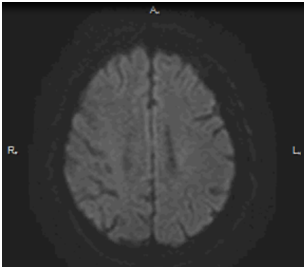

Выполнено МРТ головного мозга в режиме DWI: постинсультные изменения в теменно-затылочной области справа размерами 40x34x25 мм, мелкие сосудистые очаги, асимметрия полушарий мозга.

МРТ головного мозга в режиме DWI в 1-е сутки после операции: очагов повышенного МР-сигнала в веществе головного мозга не выявлено в режиме DWI b =1000.